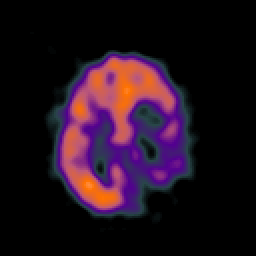

SPECT TC Study #4 -- Slice #38

[Home][Help][Clinical][Tour 1][Tour 2][Tour 3] Slice 38